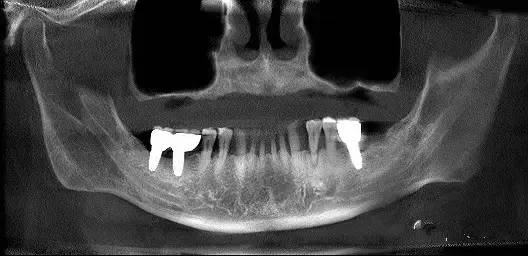

第四圖:上頜竇發(fā)育不足,上頜竇底骨高度充裕,通常頰側(cè)骨壁超級厚,看下圖2.臨床上種植常不需要提升措施。(如需提升,切記頰側(cè)骨厚度過大,開窗的困難性劇增)